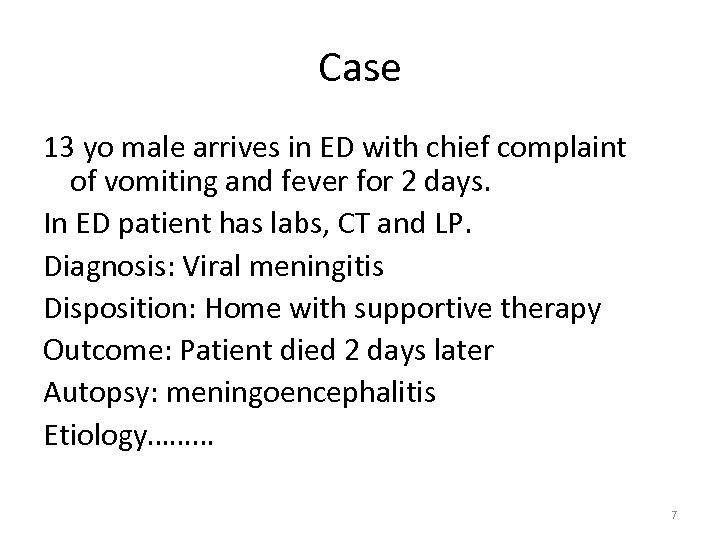

Case 13 yo male arrives in ED with chief complaint of vomiting and fever for 2 days. In ED patient has labs, CT and LP. Diagnosis: Viral meningitis Disposition: Home with supportive therapy Outcome: Patient died 2 days later Autopsy: meningoencephalitis Etiology……… 7